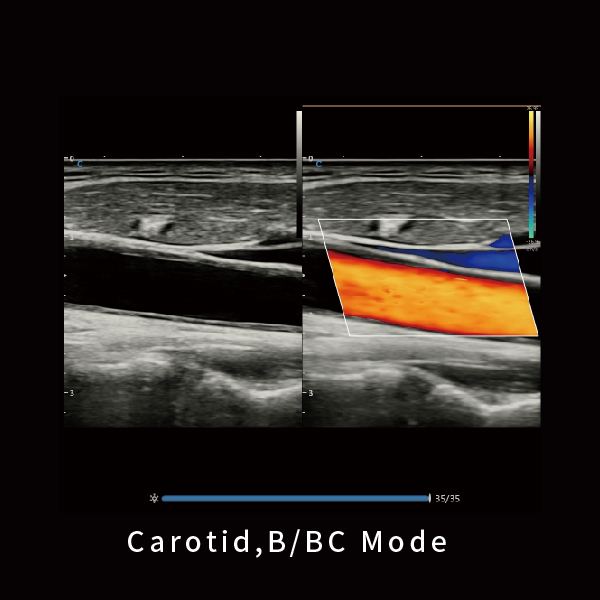

颈动脉 B BC模式